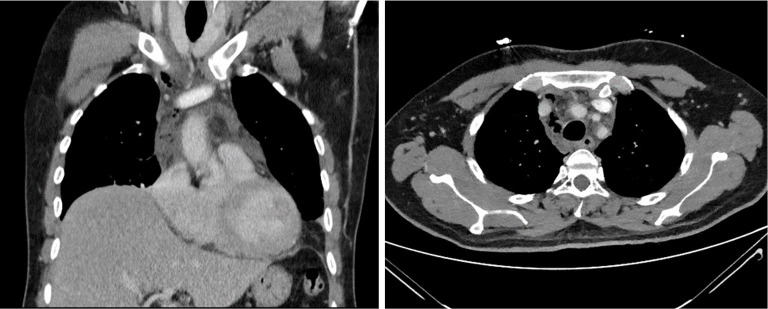

Case description: We analyze a retrospective case series of seven patients diagnosed with DNM between March 2019 and July 2022 at Hospital de la Santa Creu i Sant Pau. The primary oropharyngeal infection was peritonsillar abscess in three cases and odontogenic abscess in four. All patients showed symptoms of severe cervical infection and symptoms suggestive of mediastinitis. A cervicothoracic computed tomography (CT) scan confirmed the presence of cervical and mediastinal collections and emphysema in all cases. All patients were simultaneously evaluated by the otorhinolaryngology and thoracic surgery teams. Broad-spectrum antibiotic therapy was instituted pending culture. All the patients underwent urgent surgery, consisting of cervicotomy to control the cervical focus and unilateral or bilateral video-assisted thoracoscopic debridement and drain of the pleural cavities and mediastinum. Regarding the outcomes, no patients died, one patient (14.2%) underwent transcervical mediastino-thoracoscopy drainage only. In six patients (85.8%) we performed a combined transcervical and transthoracic approach. Reoperation was required in 3 (43%) cases. The parameter that indicated a poor clinical evolution in these patients was an increase in C-reactive protein and the infection extension on the cervicothoracic CT scan. The follow-up was 30 days from last surgery; there were no losses.

Abstract Image